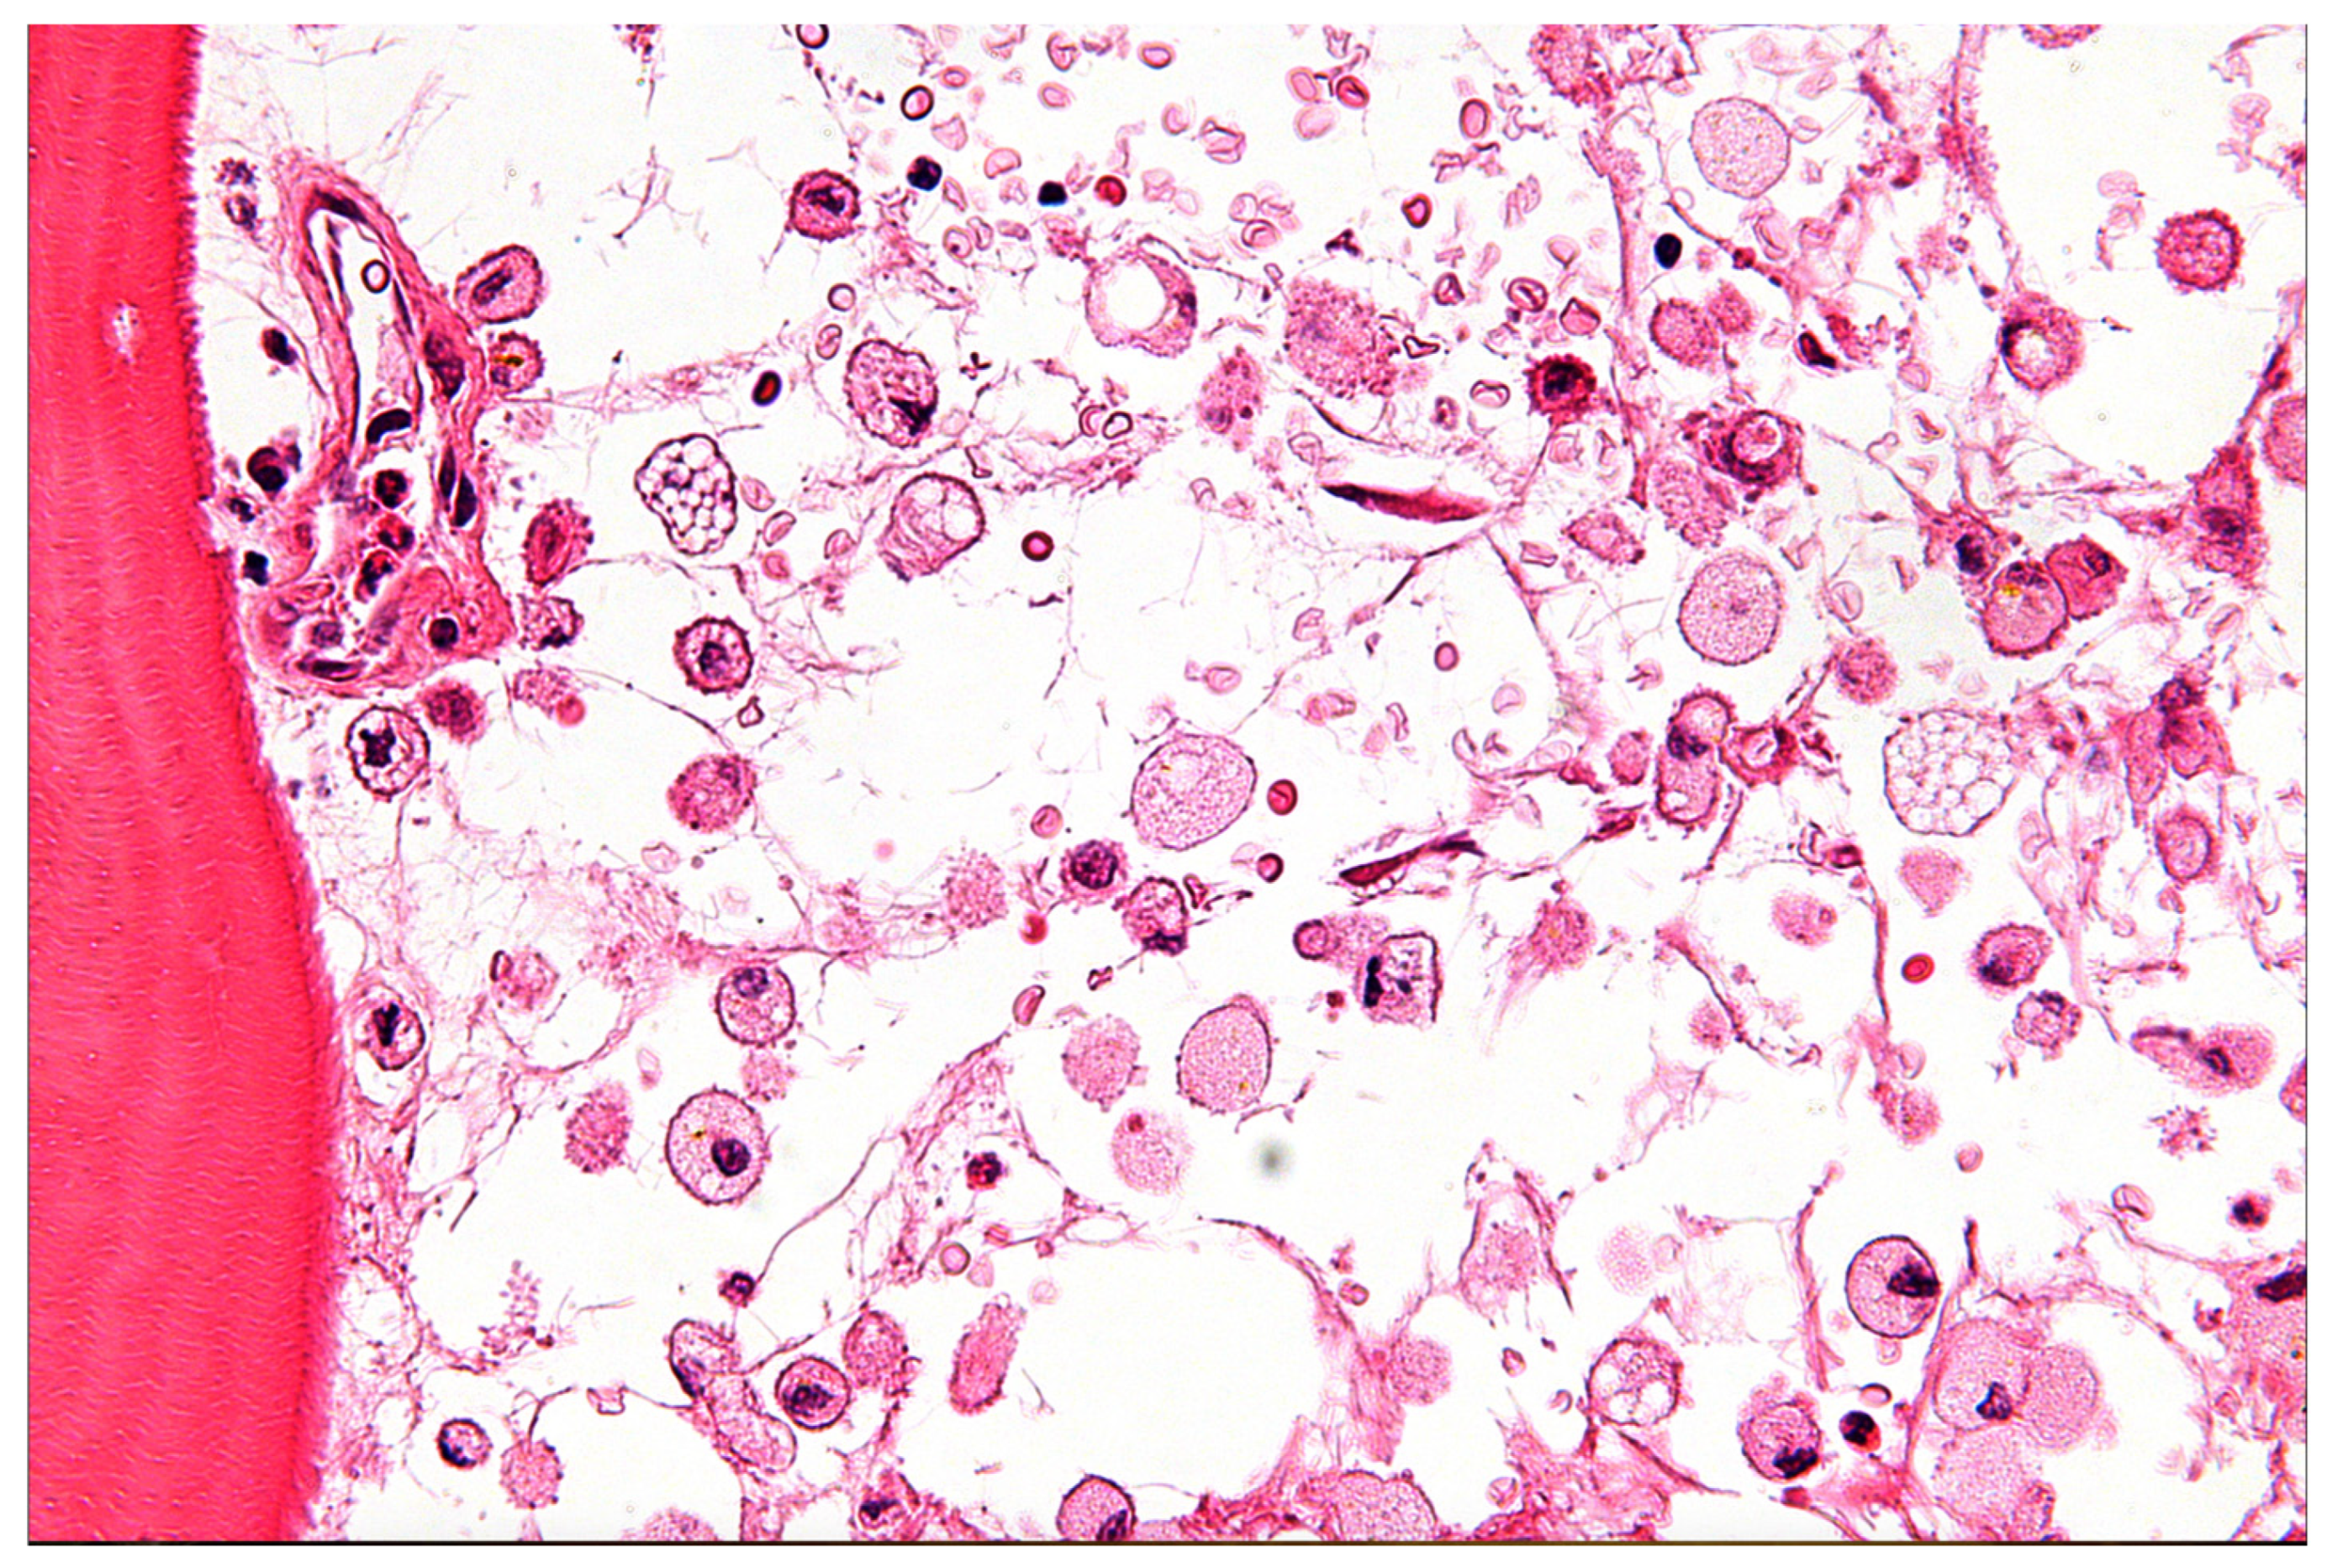

| Mitochondrial Encephalopathies [21,24,25,27,28] | MELAS | Stroke-like episodes (pre-40), encephalopathy (seizures/dementia), lactic acidosis (blood/CSF), myopathy, recurrent headaches, short stature, hearing impairment. | Increased Blood/CSF lactate, Increased lactate: pyruvate, muscle biopsy (ragged red fibers), mtDNA genetic testing. | Non-specific lactic acidosis, heteroplasmy/tissue distribution challenges for genetic testing, muscle biopsy not always definitive, neuroimaging non-specific. |

- File:Modified Gomori Trichrome Stain Showing Several Ragged Red Fibers.jpg. Wikimedia Commons. 2023. Available online: https://commons.wikimedia.org/w/index.php?title=File:Modified_Gomori_trichrome_stain_showing_several_ragged_red_fibers.jpg&oldid=763868130 (accessed on 30 June 2025).

- File:Gaucher Disease—Very High Mag.jpg. Wikimedia Commons. 2024. Available online: https://commons.wikimedia.org/w/index.php?title=File:Gaucher_disease_-_very_high_mag.jpg&oldid=890184076 (accessed on 30 June 2025).